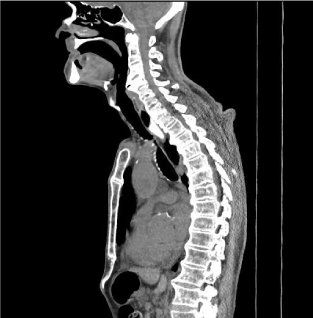

Due to the appearance of dysphonia and aggravation of dysphagia, he was admitted. Patient presented malnourished and dehydrated, with muscle flaccidity, cervical and axial skeletal rigidity. Another UDE was performed (Figure 3), which showed a bulge in the hypopharynx due to external compression – dysphagia lusoria. Computed Tomography (CT) (Figures 4 and 5) presented degenerative alterations affecting the cervical vertebrae with osteophytosys, reduction of discal spaces, subchondral cysts and anterior bridges syndesmotic. At the C3-C4 level, there was a large anterior osteophyte, which compressed the upper esophagus at the level of the vestibular fold (Figures 6,7 and 8). Due to malnutrition and repetitive aspiration pneumonias, feeding was started through a nasoenteral tube. Patient was referred for orthopedic surgeon to perform definitive treatment with resection of the cervical osteophyte.

Figure 4. Computed Tomography: diffuse skeletal hyperostosis

Figure 5. Computed Tomography: diffuse skeletal hyperostosis

Figure 6.  Computed Tomography: anterior cervical osteophyte formation

Figure 7. Computed Tomography: anterior cervical osteophyte formation.

Figure 8. Computed Tomography: anterior cervical osteophyte formation.